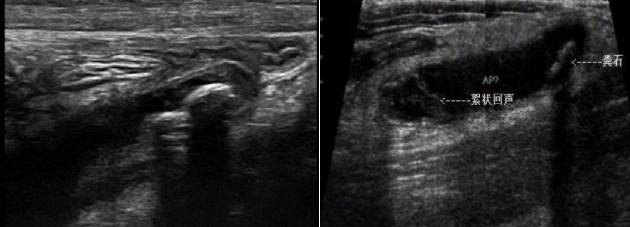

不可壓縮、腔內(nèi)積液/糞石(強(qiáng)回聲伴聲影)。

闌尾顯著腫脹,漿膜高度充血,被纖維蛋白與膿性滲出物覆蓋,或大網(wǎng)膜包裹,闌尾腔內(nèi)積膿,腔壁小膿腫形成。超聲圖:闌尾明顯增粗,外徑>10mm,闌尾壁明顯增厚,呈不均勻低回聲,各層次厚薄不一,壁內(nèi)彩色血流豐富。部分腔內(nèi)可見積液或絮狀沉積物或糞石。腹腔可見渾濁滲出液或膿液。

壞疽性闌尾炎管壁缺血壞死,易繼發(fā)穿孔,且周圍滲出液較多。聲像圖:闌尾明顯腫脹,直徑常>1.5cm,闌尾壁結(jié)構(gòu)不清,粘膜層及粘膜下層斷續(xù)、消失,腔內(nèi)可見點(diǎn)狀絮狀膿液回聲。闌尾穿孔時(shí),闌尾壁連續(xù)性中斷,闌尾內(nèi)腔部分或全部消失,右下腹闌尾區(qū)可見積液。